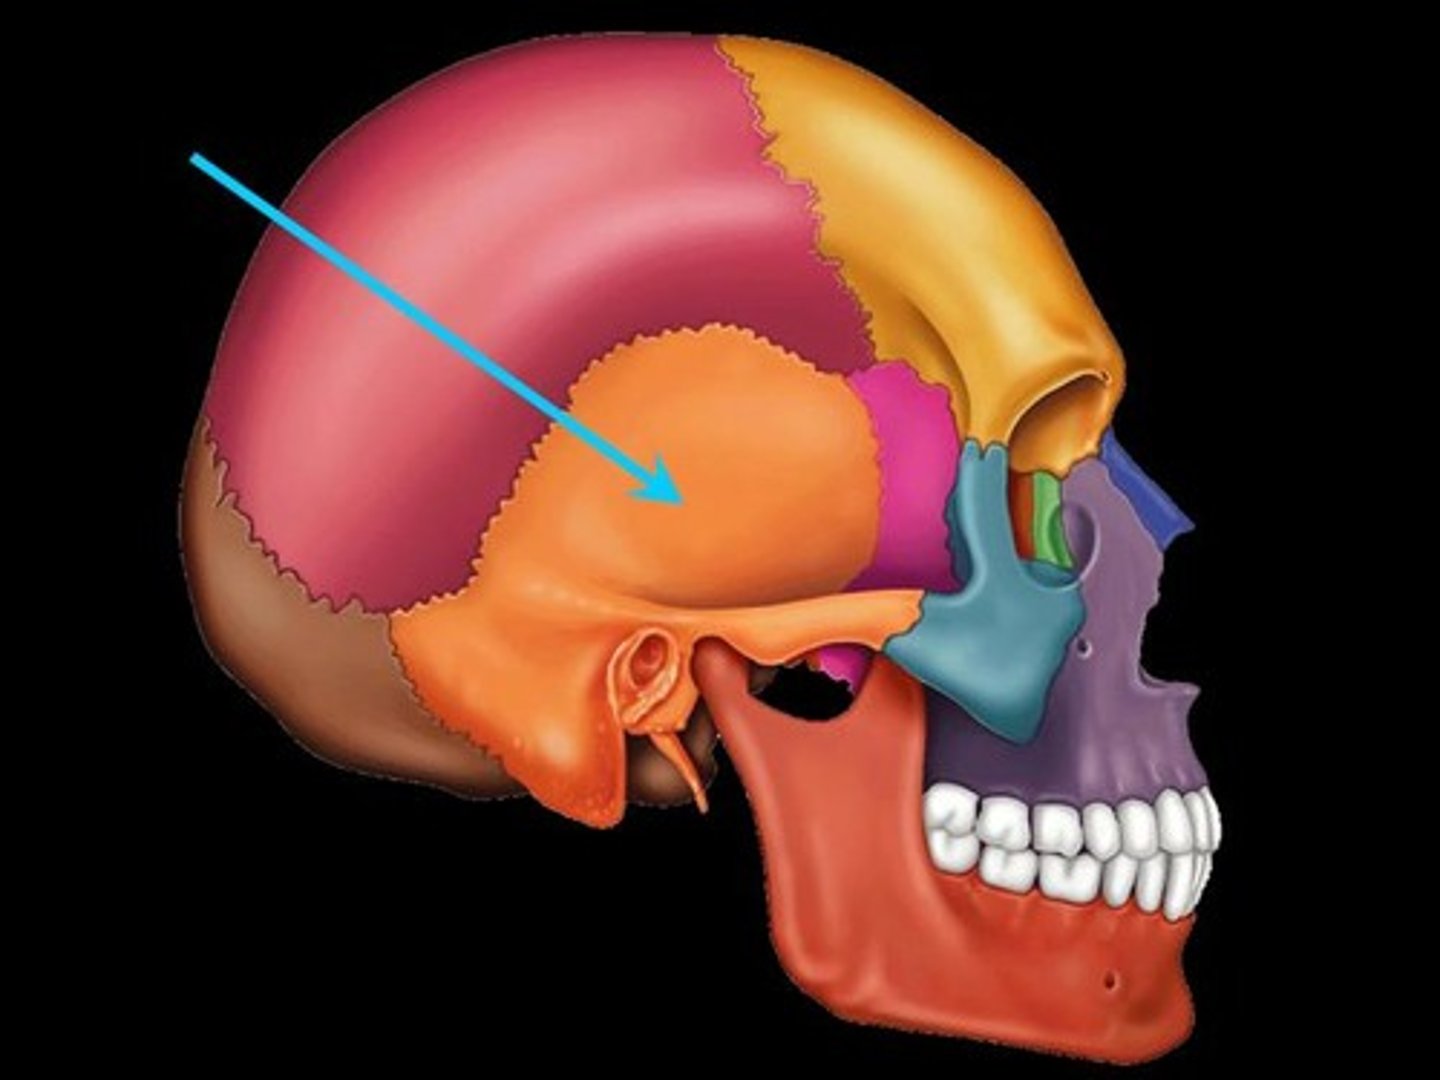

Temporal Bones

The lateral bones on each side of the cranium; the temples

Temporalis

A broad, fan-shaped muscle on each side of the head that fills the temporal fossa, superior to the zygomatic arch so it covers much of the temporal bone